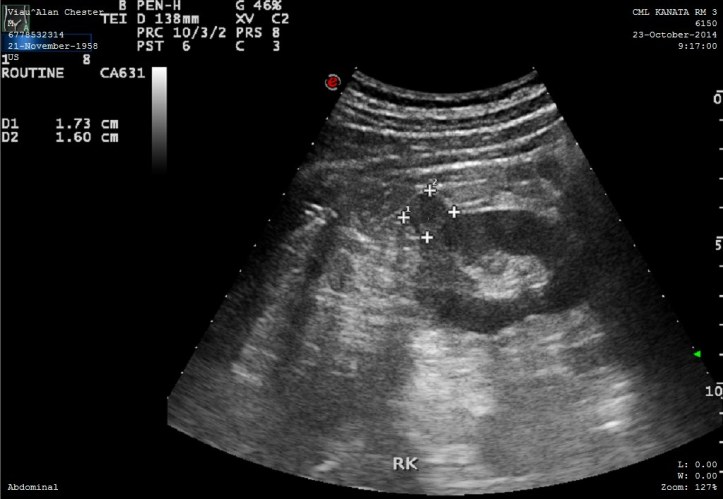

Ultrasound Right Kidney

Ultrasound of my right kidney showing tumor growth

I am now in the hospital recovering from having the kidney tumor removed. Even though not malignant it was still growing and needed to be extracted. As a bonus, the doc took out a kidney stone while in there.